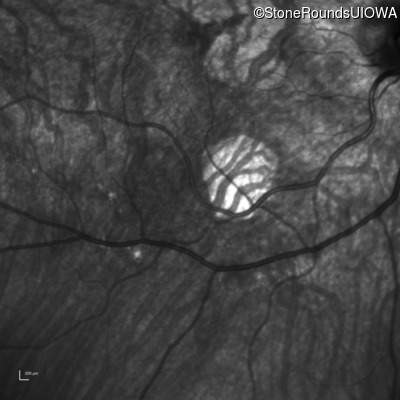

Optical Coherence Tomography - Left - 20/60 +2 sc

Exemplar / OCT Stack